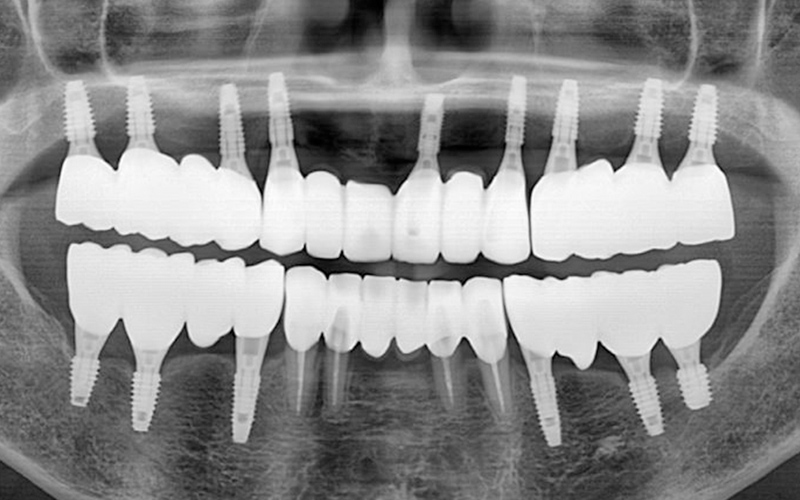

전악 임플란트는 임플란트 틀니보다 씹는 힘이 훨씬 좋습니다.

내 치아처럼 사용이 가능하며

전체 치아 기능의 90% 정도로 회복력이 좋습니다.